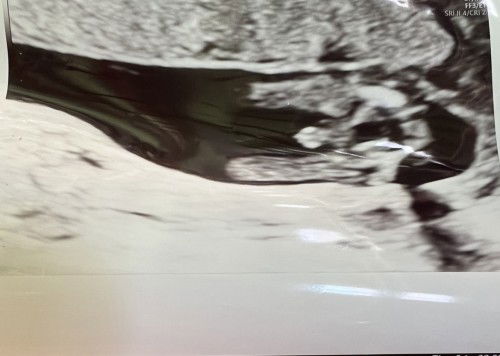

แม่ๆ ช่วยดูเพศน้องให้หน่อยค่า

แม่ๆ ช่วยดูเพศน้องให้หน่อยค่า เมื่อวันที่ 22 ส.ค.65 ไปตรวจคัดกรองฯ ได้ 2 ภาพนี้มาค่ะ หมอบอกว่าเพศชายค่ะ ดีใจมากเลย แต่วันนี้นัดตรวจปกติ หมออัลตราซาวด์มองไม่เห็นกระปู๋ซะงั้น บอกว่าสายสะเดือมาบังอยู่ค่ะ เลยอยากรู้ว่าภาพที่ได้มาลูกจะเป็นเพศชายแน่มั๊ยคะ ที่เห็นเป็นกระปู๋หรือเป็นอย่างอื่นไปได้มั้ยคะ

น่าจะชายนะคะ